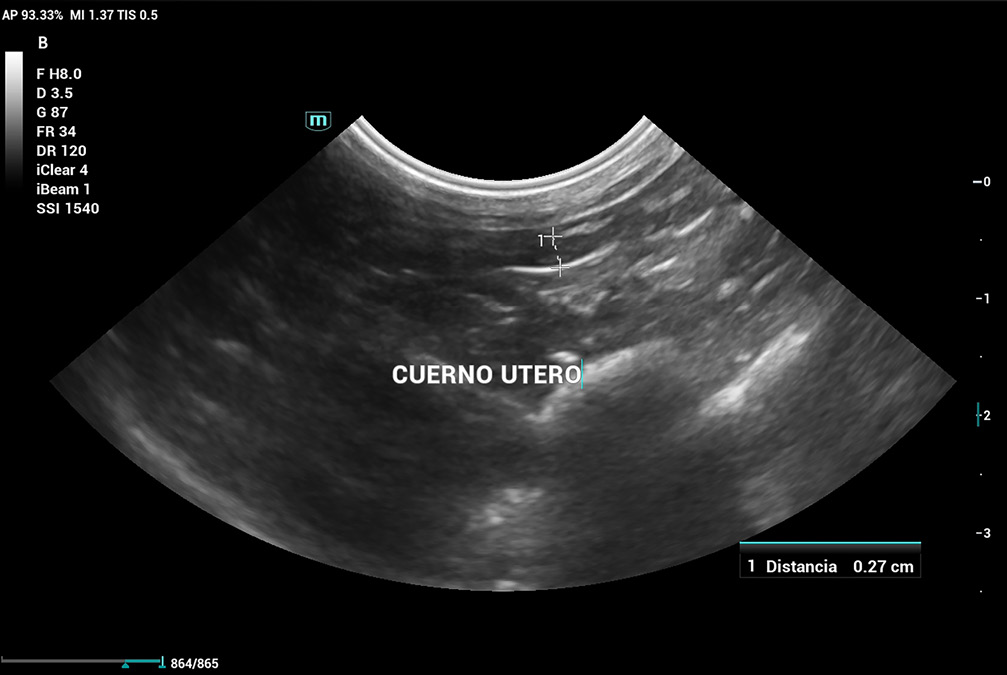

Se realiza ecografía abdominal, que evidencia que aún cuenta con cuernos uterinos (imagen 6), lo que confirma la ovariectomía (no ovariohisterectomía). Por este motivo, se decide enviar una muestra de plasma sanguíneo a un laboratorio externo para evaluar los niveles de 17β-estradiol, dado que en ecografía no se logra distinguir con claridad un remanente ovárico.